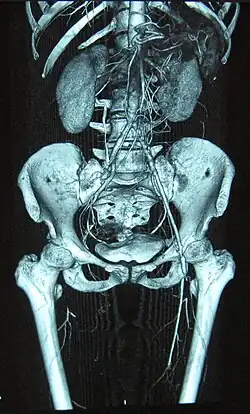

| Complete occlusion of the right and stenosis of the left femoral artery as seen in a case of thromboangiitis obliterans | |

Angiograms of the upper and lower extremities can be helpful in making the diagnosis of Buerger's disease. In the proper clinical setting, certain angiographic findings are diagnostic of Buerger's. These findings include a "corkscrew" appearance of arteries that result from vascular damage, particularly the arteries in the region of the wrists and ankles. Collateral circulation gives "tree root" or "spider leg" appearance.[1] Angiograms may also show occlusions (blockages) or stenosis (narrowings) in multiple areas of both the arms and legs. Distal plethysmography also yields useful information about circulatory status in digits. To rule out other forms of vasculitis (by excluding involvement of vascular regions atypical for Buerger's), it is sometimes necessary to perform angiograms of other body regions (e.g., a mesenteric angiogram).